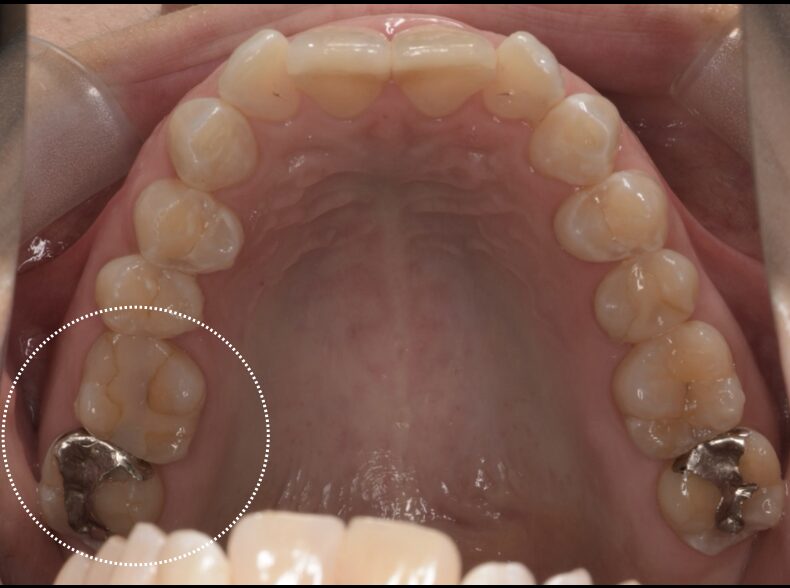

虫歯をセラミックインレー治療した症例

Before

| 治療内容 | セラミックインレー |

| 治療期間・治療回数 | 2回 |

| 治療費用 | 143000円(税込) |

| 備考 | 30代 男性 |